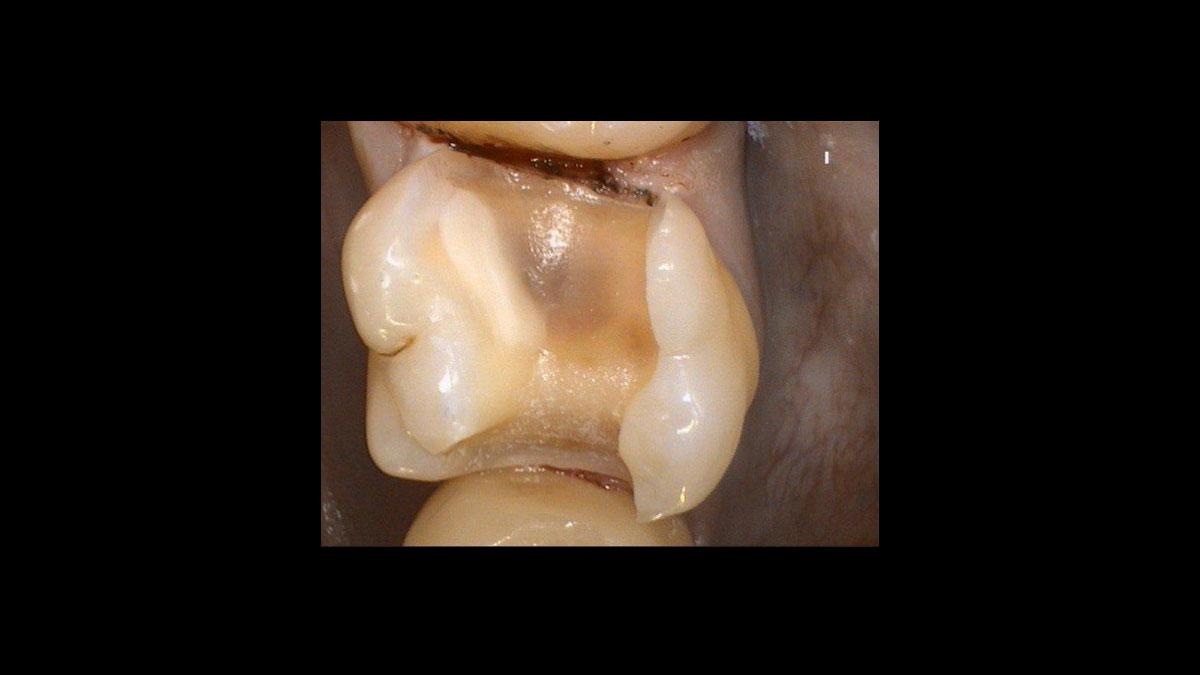

Preparación del tejido gingival antes de la toma de impresiones dentales

• Preparación del tejido gingival antes de la toma de impresiones dentales